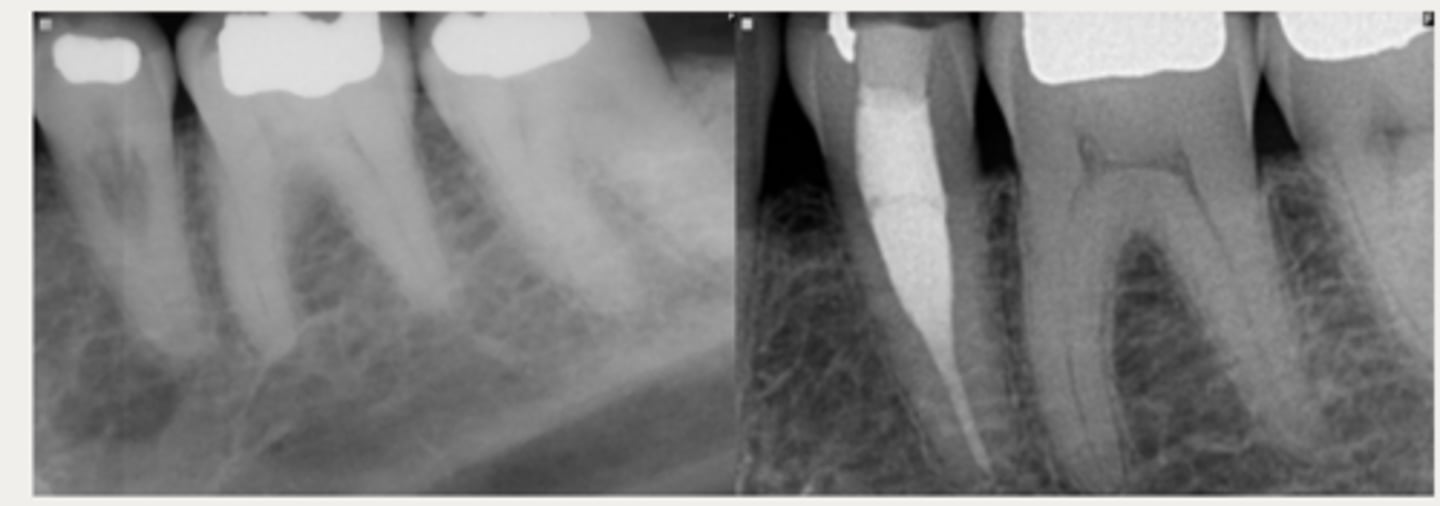

External Replacement Resorption/Ankylosis

Which type of resorption?

- Fusion of cementum or dentin with alveolar bone

Which type of resorption>

- Damage to PDL ⇒ stimulus for surrounding bone to activate osteoclasts and begin resorbing cementum/dentin and replacing it with bone tissue

- Almost always due to trauma (luxation, intrustion, avulsion, replantation)

- Can be progressive or self-limiting

ID the type of resorption:

CLINICAL

- Characteristic metallic sound on percussion

- May appear infraoccluded in developing dentition

- Lacks physiologic mobility of normal teeth

- May not respond to sensibility testing

RADIOGRAPHIC

- Absence of lamina dura/PDL

- Bone trabeculation occupying previous root surface

- CBCT is often helpful to assess the full extent

Patient presents with a metallic sound on percussion, infraoccluded appearance in developing dentition and may not respond to sensibility testing. What is the most likely diagnosis?

Patient presents with these radiographic findings. What is the most likely diagnosis?

- Absence of lamina dura/PDL around lesion.

- Bone trabeculation occupying previous root surface.